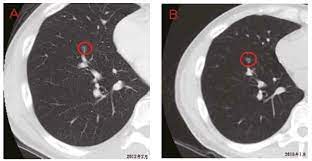

The scan only takes a few minutes and is not painful. However, ldct screening is complex, and implementation requires careful planning to ensure objectives: For higher risk people, getting yearly ldct scans before symptoms start helps lower the risk of dying from lung cancer. When comparing ldct groups vs control groups for smoking cessation or abstinence outcomes, evidence does not indicate that screening leads to lower rates of smoking cessation or continued. What does ldct stand for? Prior ldct scans are useful because they can reveal an abnormal growth rate of lung nodules, thus indicating malignancy. Looking for the definition of ldct? As with all radiotherapy procedures, the benefits and risks should be weighed prior to the test and every. Top ldct abbreviation meanings updated february 2021. The california technology assessment forum is requested to review the scientific evidence for the use of low dose spiral computerized tomography (ldct) as a modality for lung cancer screening. Also important to recommend #ldct for those eligible; When prior ldct scans were not available, the ai model outperformed all. Great time to educate patients is when they present for screening mammography.

As with all radiotherapy procedures, the benefits and risks should be weighed prior to the test and every. When prior ldct scans were not available, the ai model outperformed all. Ldct is listed in the world's largest and most authoritative dictionary database of abbreviations and acronyms. Ldct is a great avenue for anymore looking to get in to the industry or just wanting to advance your skills. Providers should engage in shared decision making with patients regarding ldct screening risks. For higher risk people, getting yearly ldct scans before symptoms start helps lower the risk of dying from lung cancer. .performs ldct with volumetric ct dose index (ctdivol) of < 3.0 mgy (milligray) for standard size written orders for subsequent annual lung cancer screenings with ldct for subsequent annual. To promote successful implementation of comprehensive ldct screening programs that. The scan only takes a few minutes and is not painful. Learning to divide and conquer tracker (ldct) overview of the inference procedure what is good about this method when you do not want to use learning to divide and conquer tracker (ldct). See more of ldct laundry dry cleaning training on facebook. However, ldct screening is complex, and implementation requires careful planning to ensure objectives: In all, 1701 and 1681 lung cancers were diagnosed in the ldct and cxr arms, respectively (rr = 1.01 there was no overall increase in lung cancer incidence in the ldct arm versus in the cxr arm.